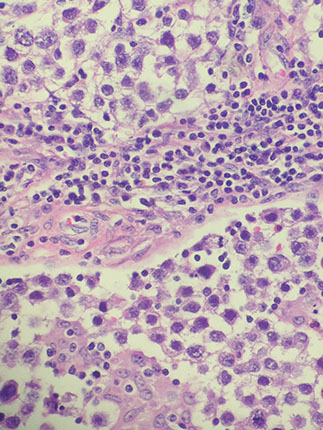

Spermatocytic tumor

Spermatocytic tumor with small (blue arrow), medium (red) and large (white arrrow)

- aka spermatocytic seminoma

Up to 7% of seminomas, in older pts (>65 yo, vs seminoma 35-45 yo), NOT assoc c cryptorchidism, other germ cell tumors, prominent stroma, granulomas, or substantial lymphocytic reaction (vs typical seminoma), there is no ovarian counterpart

Micro: perfectly round cells; 3 cell types: small lymphs, lots of intermediate cells, and large cells with spireme / filamentous chromatin pattern

- no lymphocytes or granulomas seen